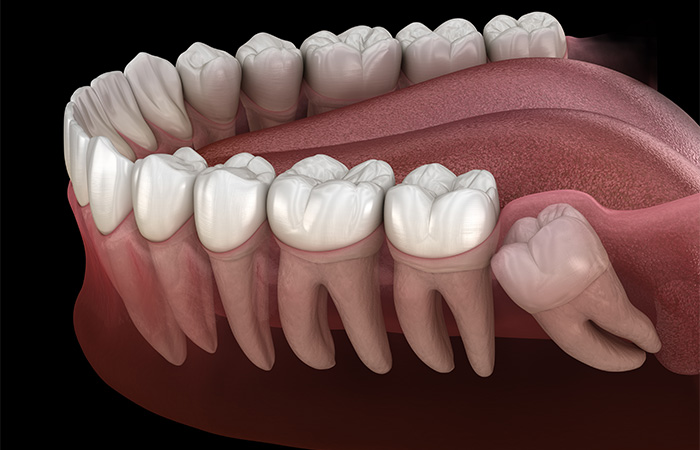

横向きに生えている

歯並びに影響したり、腫れや痛みが出たりする恐れがあるため、抜歯を検討します。

完全に埋まっている

ほかの歯に影響がなければ、抜歯が不要と判断されることもありますが、歯並びの乱れや顎関節症の原因となる場合は抜歯を検討します。